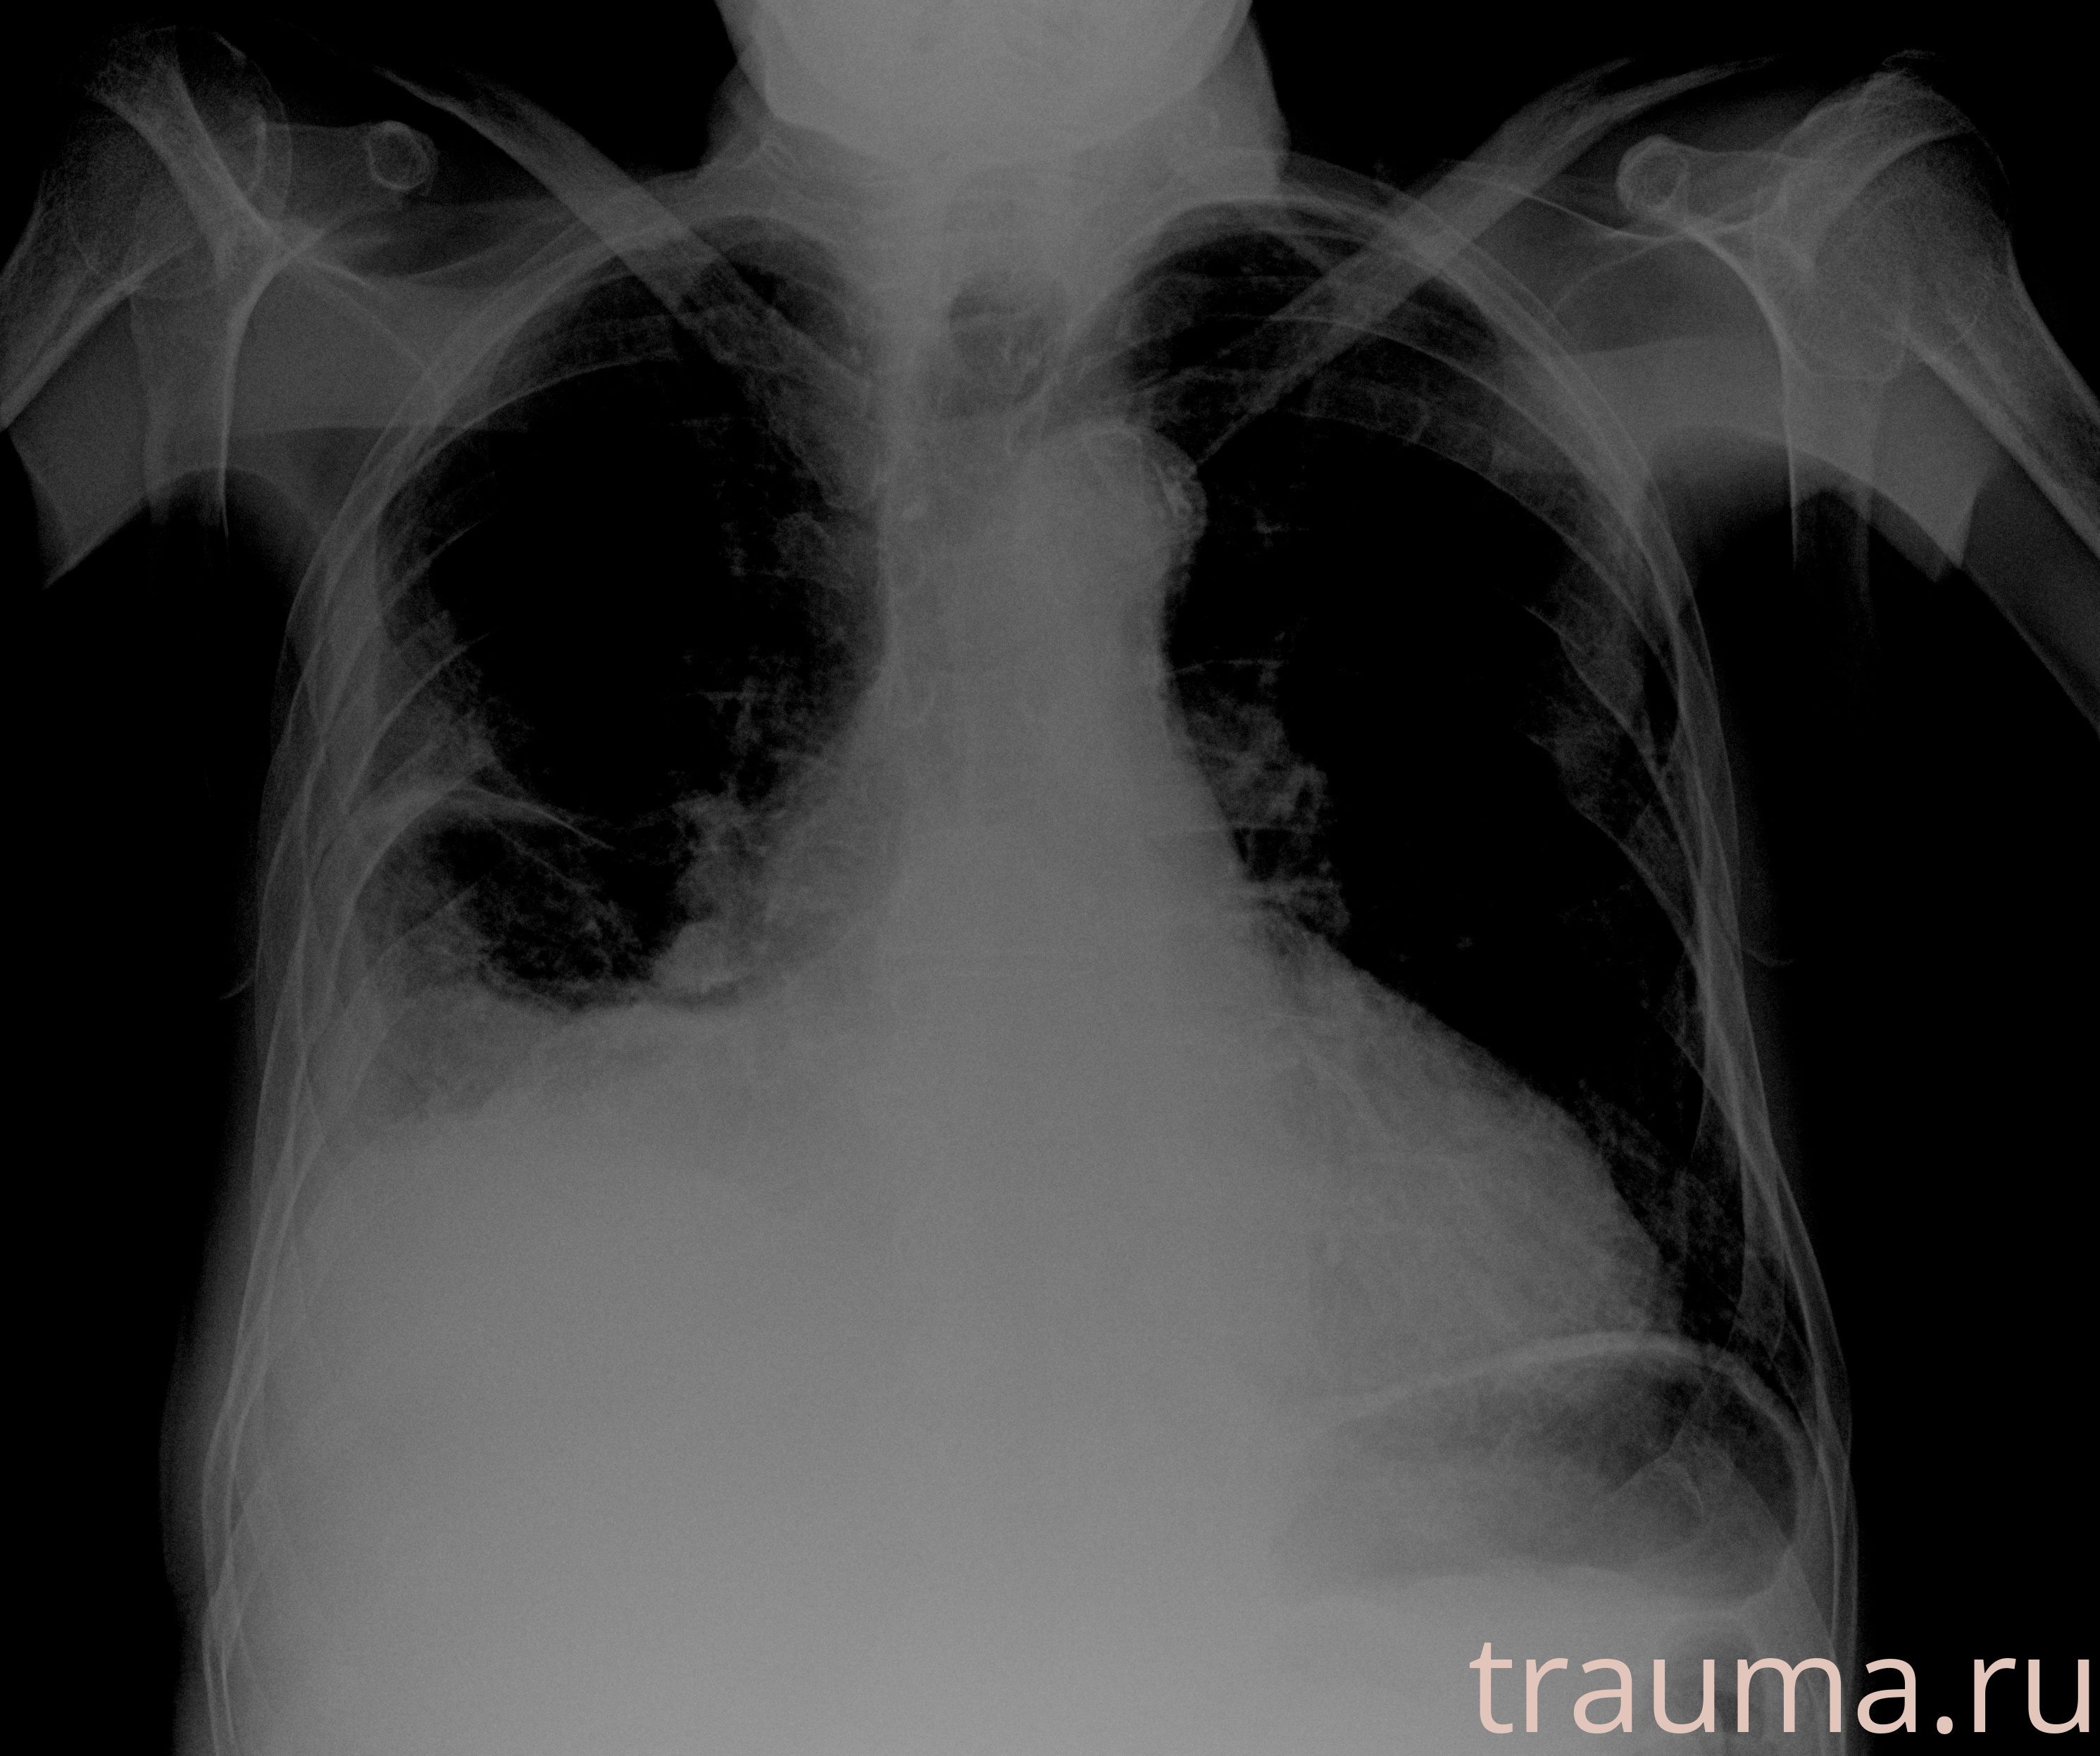

Рентген на дому: по вашему адресу приезжает врач-рентгенолог, травматолог-ортопед с мобильным рентгеновским аппаратом, проводит диагностику травмы или заболевания, делает необходимые рентгенограммы, дает рекомендации по дальнейшему лечению. Получить качественные снимки в домашних условиях возможно благодаря уникальной методике, разработанной МосРентген Центром для института  Склифосовского

при переломе шейки бедра и пневмонии от компании МосРентген Центр - партнера Института имени Склифосовского